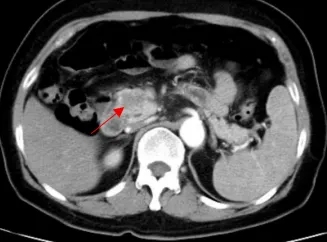

70岁、76岁、82岁,河北医大二院成功实施三例高难度腹膜后巨大肿瘤切除术

箭头示为患者三的胰头部恶性肿瘤

箭头示为患者三的腹膜后肿瘤 延伸至盆腔